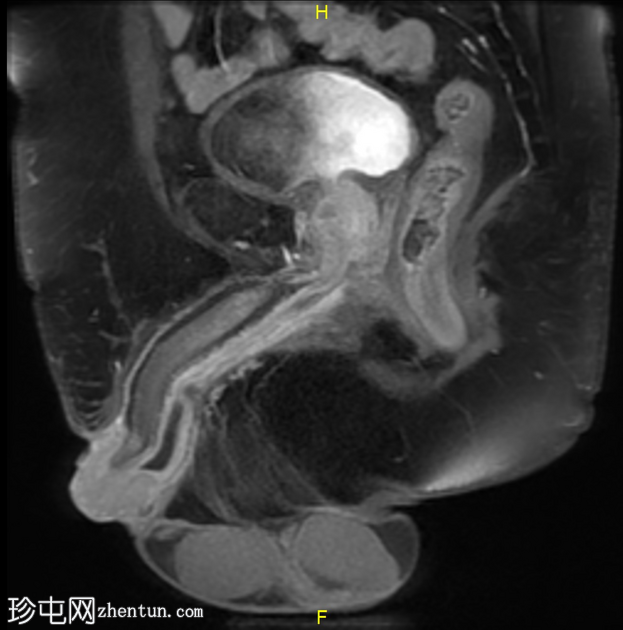

MRI

1.png

矢状位

T2加权像

龟头可见不规则形状的软组织肿块,增强后明显强化,并伴有扩散受限。该肿块侵犯尿道海绵体,导致远端尿道狭窄和上游尿道扩张。

左侧腹股沟可见多个肿大的病理性淋巴结,右侧可见较小的非特异性淋巴结。